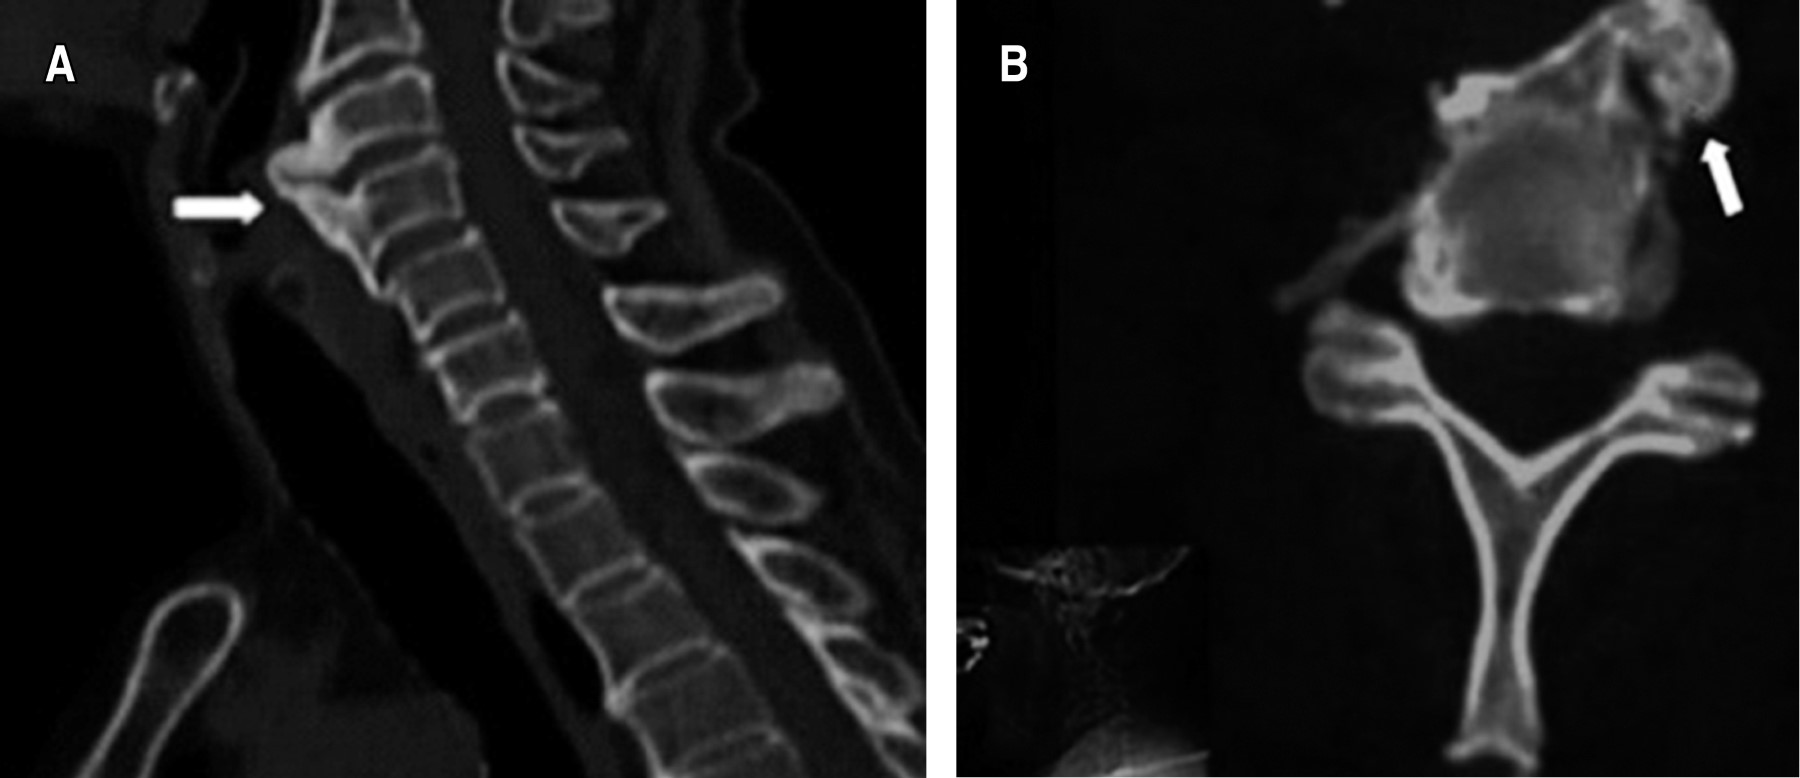

El diagnóstico de DISH en todos los casos se puede realizar con radiografías simples, aunque se pueden hacer estudios adicionales como TAC y resonancia magnética (RM).13

Cabe mencionar que las fracturas cervicales en DISH ocurren principalmente a nivel de los discos intervertebrales. La columna cervical es el segundo segmento más afectado, siendo C5 y C6 los cuerpos vertebrales más afectados.2,14

Dentro de las características radiográficas para diagnosticar DISH se pueden encontrar criterios de diversos autores. Sin embargo, en la actualidad prevalecen los de Resnick-Niwayama, aunque estos criterios se limitan a identificar pacientes en la etapa avanzada de la enfermedad (Tabla 1).13

Se pueden identificar diferentes signos en los estudios de imagen que pueden orientar al diagnóstico de DISH antes de que avance más la enfermedad. En un inicio el proceso de hiperostosis se desarrolla en la plataforma inferior del cuerpo anterior de la vértebra dando como resultado el signo "de la gota que cae" (Figura 1).14

Posteriormente el tejido óseo crece formando espolones o entesofitos y se expanden a la plataforma superior del cuerpo, formando así los característicos puentes intervertebrales y otros signos como "cera de vela derretida" y "pico de loro" (Figuras 2 y 3).14